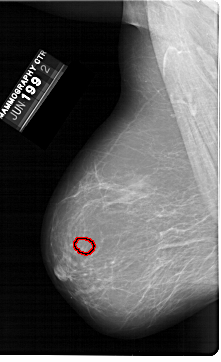

FILE: A_1398_1.LEFT_MLO.OVERLAY TOTAL_ABNORMALITIES 1 ABNORMALITY 1 LESION_TYPE MASS SHAPE LOBULATED MARGINS CIRCUMSCRIBED ASSESSMENT 3 SUBTLETY 3 PATHOLOGY BENIGN TOTAL_OUTLINES 1 BOUNDARY |